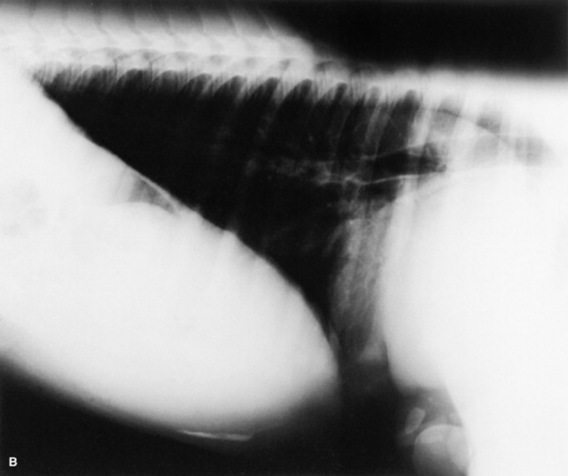

Serial thoracic radiographs are useful in monitoring the progress of a respiratory condition. Radiographic changes may either follow or precede changes in clinical condition, and major changes can occur surprisingly rapidly (Fig. 19-2). Clinical signs of pneumonia frequently resolve much earlier than chest radiographs and hemograms return to normal. Unfortunately, both ABG analysis and radiography are difficult to perform in field situations.

Fig. 19-2 A, Standing lateral chest radiograph of a 7-day-old thoroughbred filly with severe angular limb deformities that experienced an acute onset of severe respiratory distress and cyanosis after a walk outside the stall. Intubation and 100% oxygen administration raised the PaO2 to only 48 mm Hg. Severe pulmonary interstitial disease is present in the caudoventral lung fields, and the tentative diagnosis was bacterial pneumonia. No modifications were made in the treatment regimen (the same antibiotics being given for a wound were continued), and over the following 24 hours the filly clinically improved. B, Repeat radiographs taken 3 days after the first ones revealed marked resolution of the infiltrates. The diagnosis remains open, but pulmonary edema was suspected.